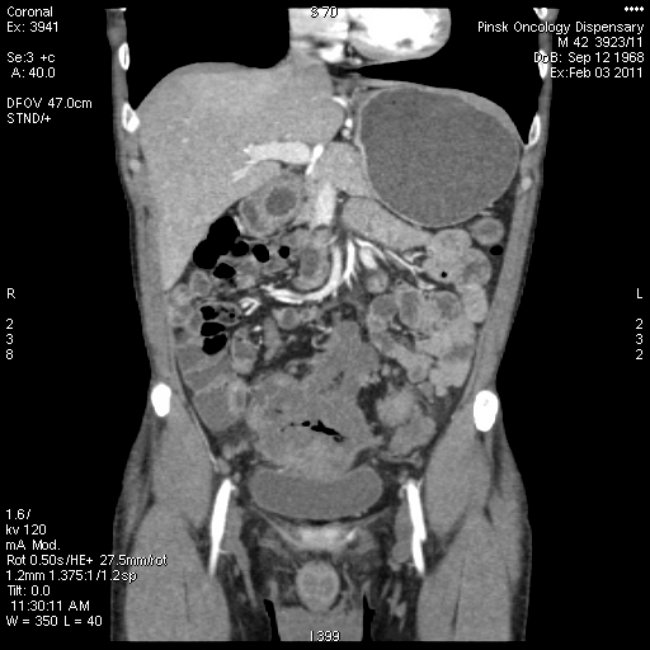

Способы диагностики аденокарциномы

Наиболее простой способ определения наличия у человека опухоли – это ее пальпация. Более подробно можно изучить состояние сигмовидной кишки путем колоноскопии – неприятной, но очень информативной процедуры, с помощью которой врач может определить наличие у пациента рака.

Для диагностики применяется рентгеноскопия сигмовидной кишки. Такая процедура называется еще и ирригоскопия. Рентгеновская диагностика применяется с помощью контрастного вещества. Так специалист может определить не только наличие в организме опухолевидного тела, но и контур, толщину кишечника, рельеф слизистой оболочки и другие особенности.

Необходимо отметить, что самым точным и совершенным способом исследования прямого кишечника является магнито-резонансная томография.

При такой диагностике врач не применяет вредное рентгеновское излучение. МРТ дает возможность определить наличие в кишечнике не только самого образование, но и на его источник и тип.